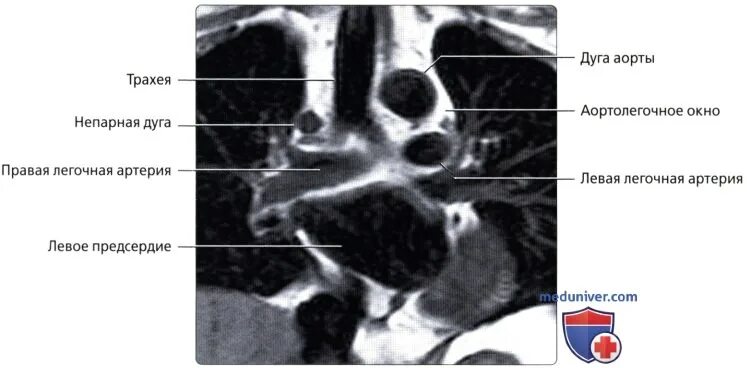

Дефект аортолегочной перегородки тест